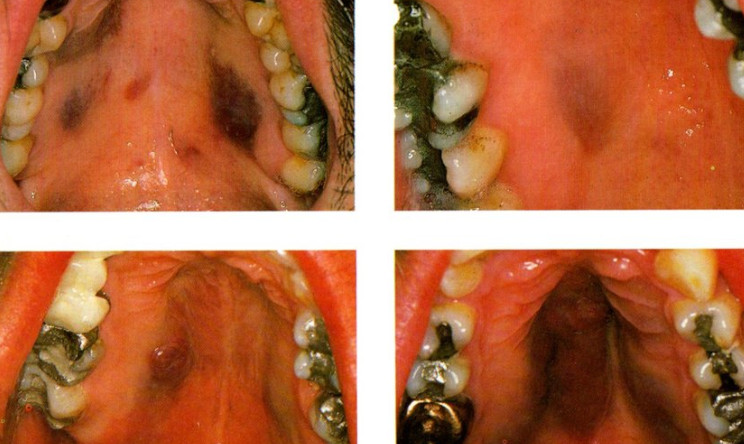

É a doença mais importante associada ao HHV-8, sendo uma desordem multifocal proliferativa de origem vascular, encontrada em quatro formas epidemiológicas mais frequentes: 1) associada à AIDS (AIDS-SK), mais observada em homens homo/bissexuais HIV-1 positivos; 2) o SK Africano (SKA), mais prevalente em certos locais da África e que corresponde a 10% dos tumores encontrados nestes locais, podendo adquirir uma forma muito agressiva após infecção por HIV-1; 3) o SK clássico (SKC) que ocorre em pacientes idosos de certas áreas do oeste do Mediterrâneo, com característica mais branda; e 4) SK associado à terapia imunossupressora pós-transplantes, denominada SK pós-transplante (PKS). A lesão é caracterizada por múltiplas manchas, de aparência nodular ou planar, principalmente nas extremidades do corpo, envolvendo mucosa e vísceras, principalmente na AIDS-SK. O estágio final é representado por uma fase tumoral nodular.